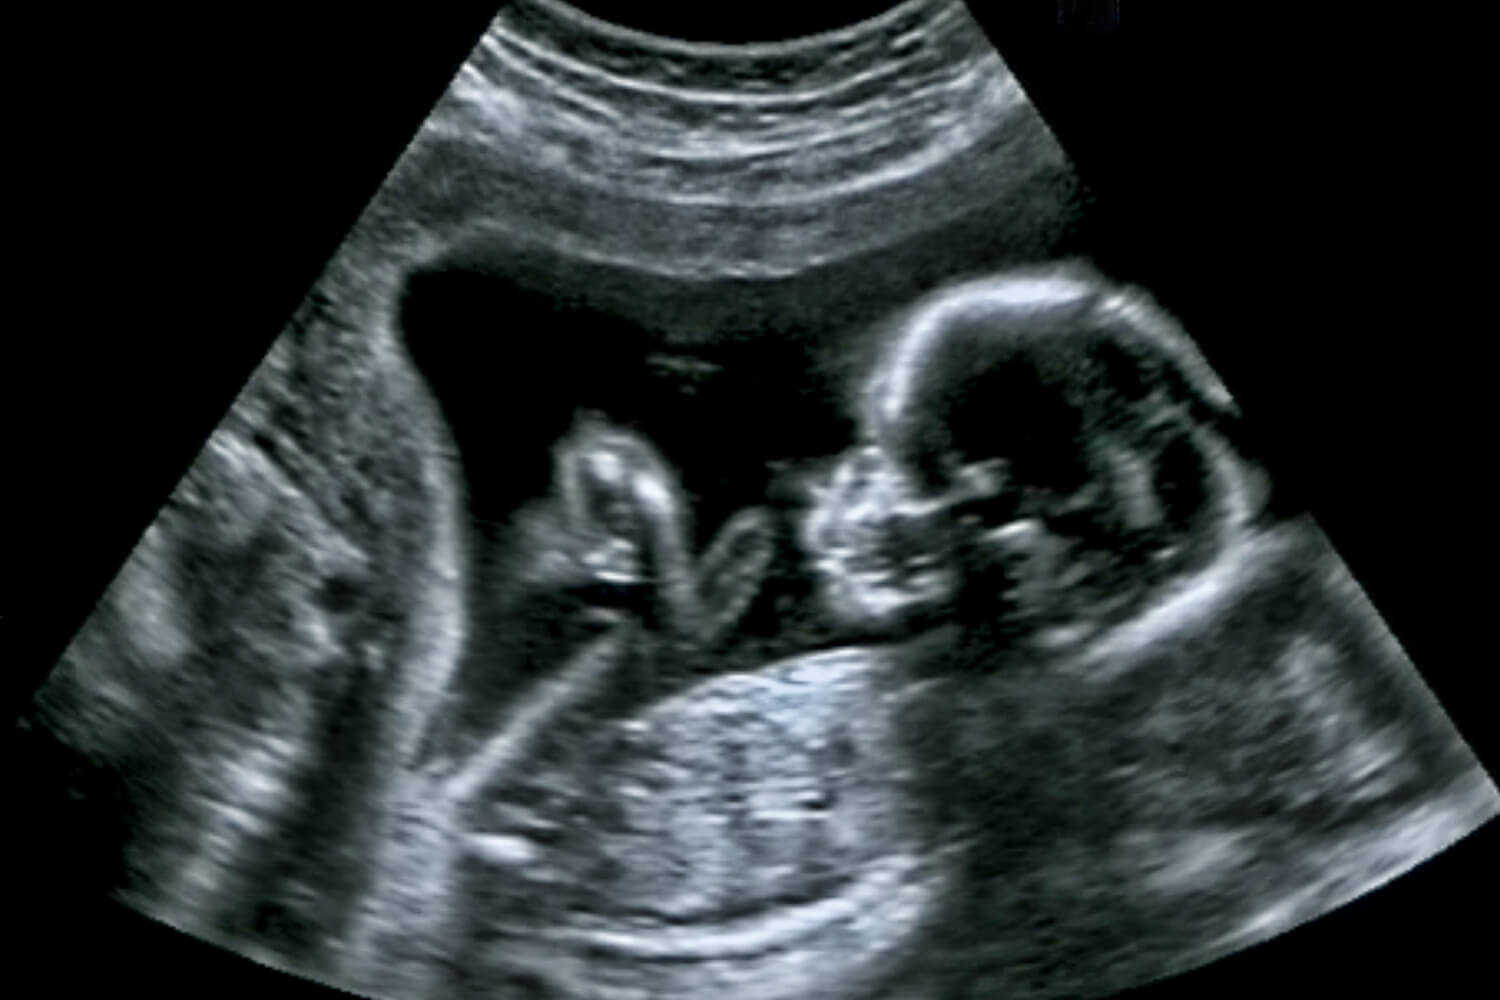

How To Check Tiffa Scan Report . The doctor will gain the following insights through the analysis of tiffa scan images: The anomaly scan or the tiffa scan examines the fetus from head to toe. You will receive a detailed scan report, which includes descriptions of the fetus’s structure, measurements, and any. Tiffa scan is the most common type of ultrasound scan or ultrasound level ii scan. However, the presence of an anomaly is likely to extend the study and make it necessary for the mother to undergo a. The facial contours of the infant and if there are any. An anomaly scan or tiffa scan (targeted imaging for fetal anomalies) is the most critical scan carried out in your second trimester. A normal tiffa scan takes approximately 1 hour to complete.

A normal tiffa scan takes approximately 1 hour to complete. An anomaly scan or tiffa scan (targeted imaging for fetal anomalies) is the most critical scan carried out in your second trimester. The anomaly scan or the tiffa scan examines the fetus from head to toe. You will receive a detailed scan report, which includes descriptions of the fetus’s structure, measurements, and any. The doctor will gain the following insights through the analysis of tiffa scan images: However, the presence of an anomaly is likely to extend the study and make it necessary for the mother to undergo a. Tiffa scan is the most common type of ultrasound scan or ultrasound level ii scan. The facial contours of the infant and if there are any.